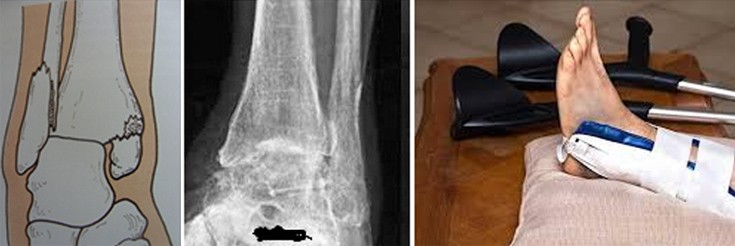

Στα κατάγματα των σφυρών επειδή διαταράσσεται η άρθρωση (υπεξάρθρημα – εξάρθρημα) μετά την κάκωση ο τραυματίας αδυνατεί να πατήσει το πόδι του και να βαδίσει και η άρθρωση φαίνεται πολύ διογκωμένη και παραμορφωμένη.

Εάν το πόδι μοιάζει να έχει «βγει» από τη θέση του, τραβώντας το πρέπει να το ανατάξουμε (να το φέρουμε στη θέση του). Κατόπιν το ακινητοποιούμε με ένα νάρθηκα.

Μετά την εγχείρηση ο τραυματίας αποφεύγει την φόρτιση του σκέλους, αρχικά με νάρθηκα και δύο πατερίτσες για 2 εβδομάδες και στη συνέχεια χωρίς νάρθηκα, κάνοντας ασκήσεις για ακόμη 4 εβδομάδες.